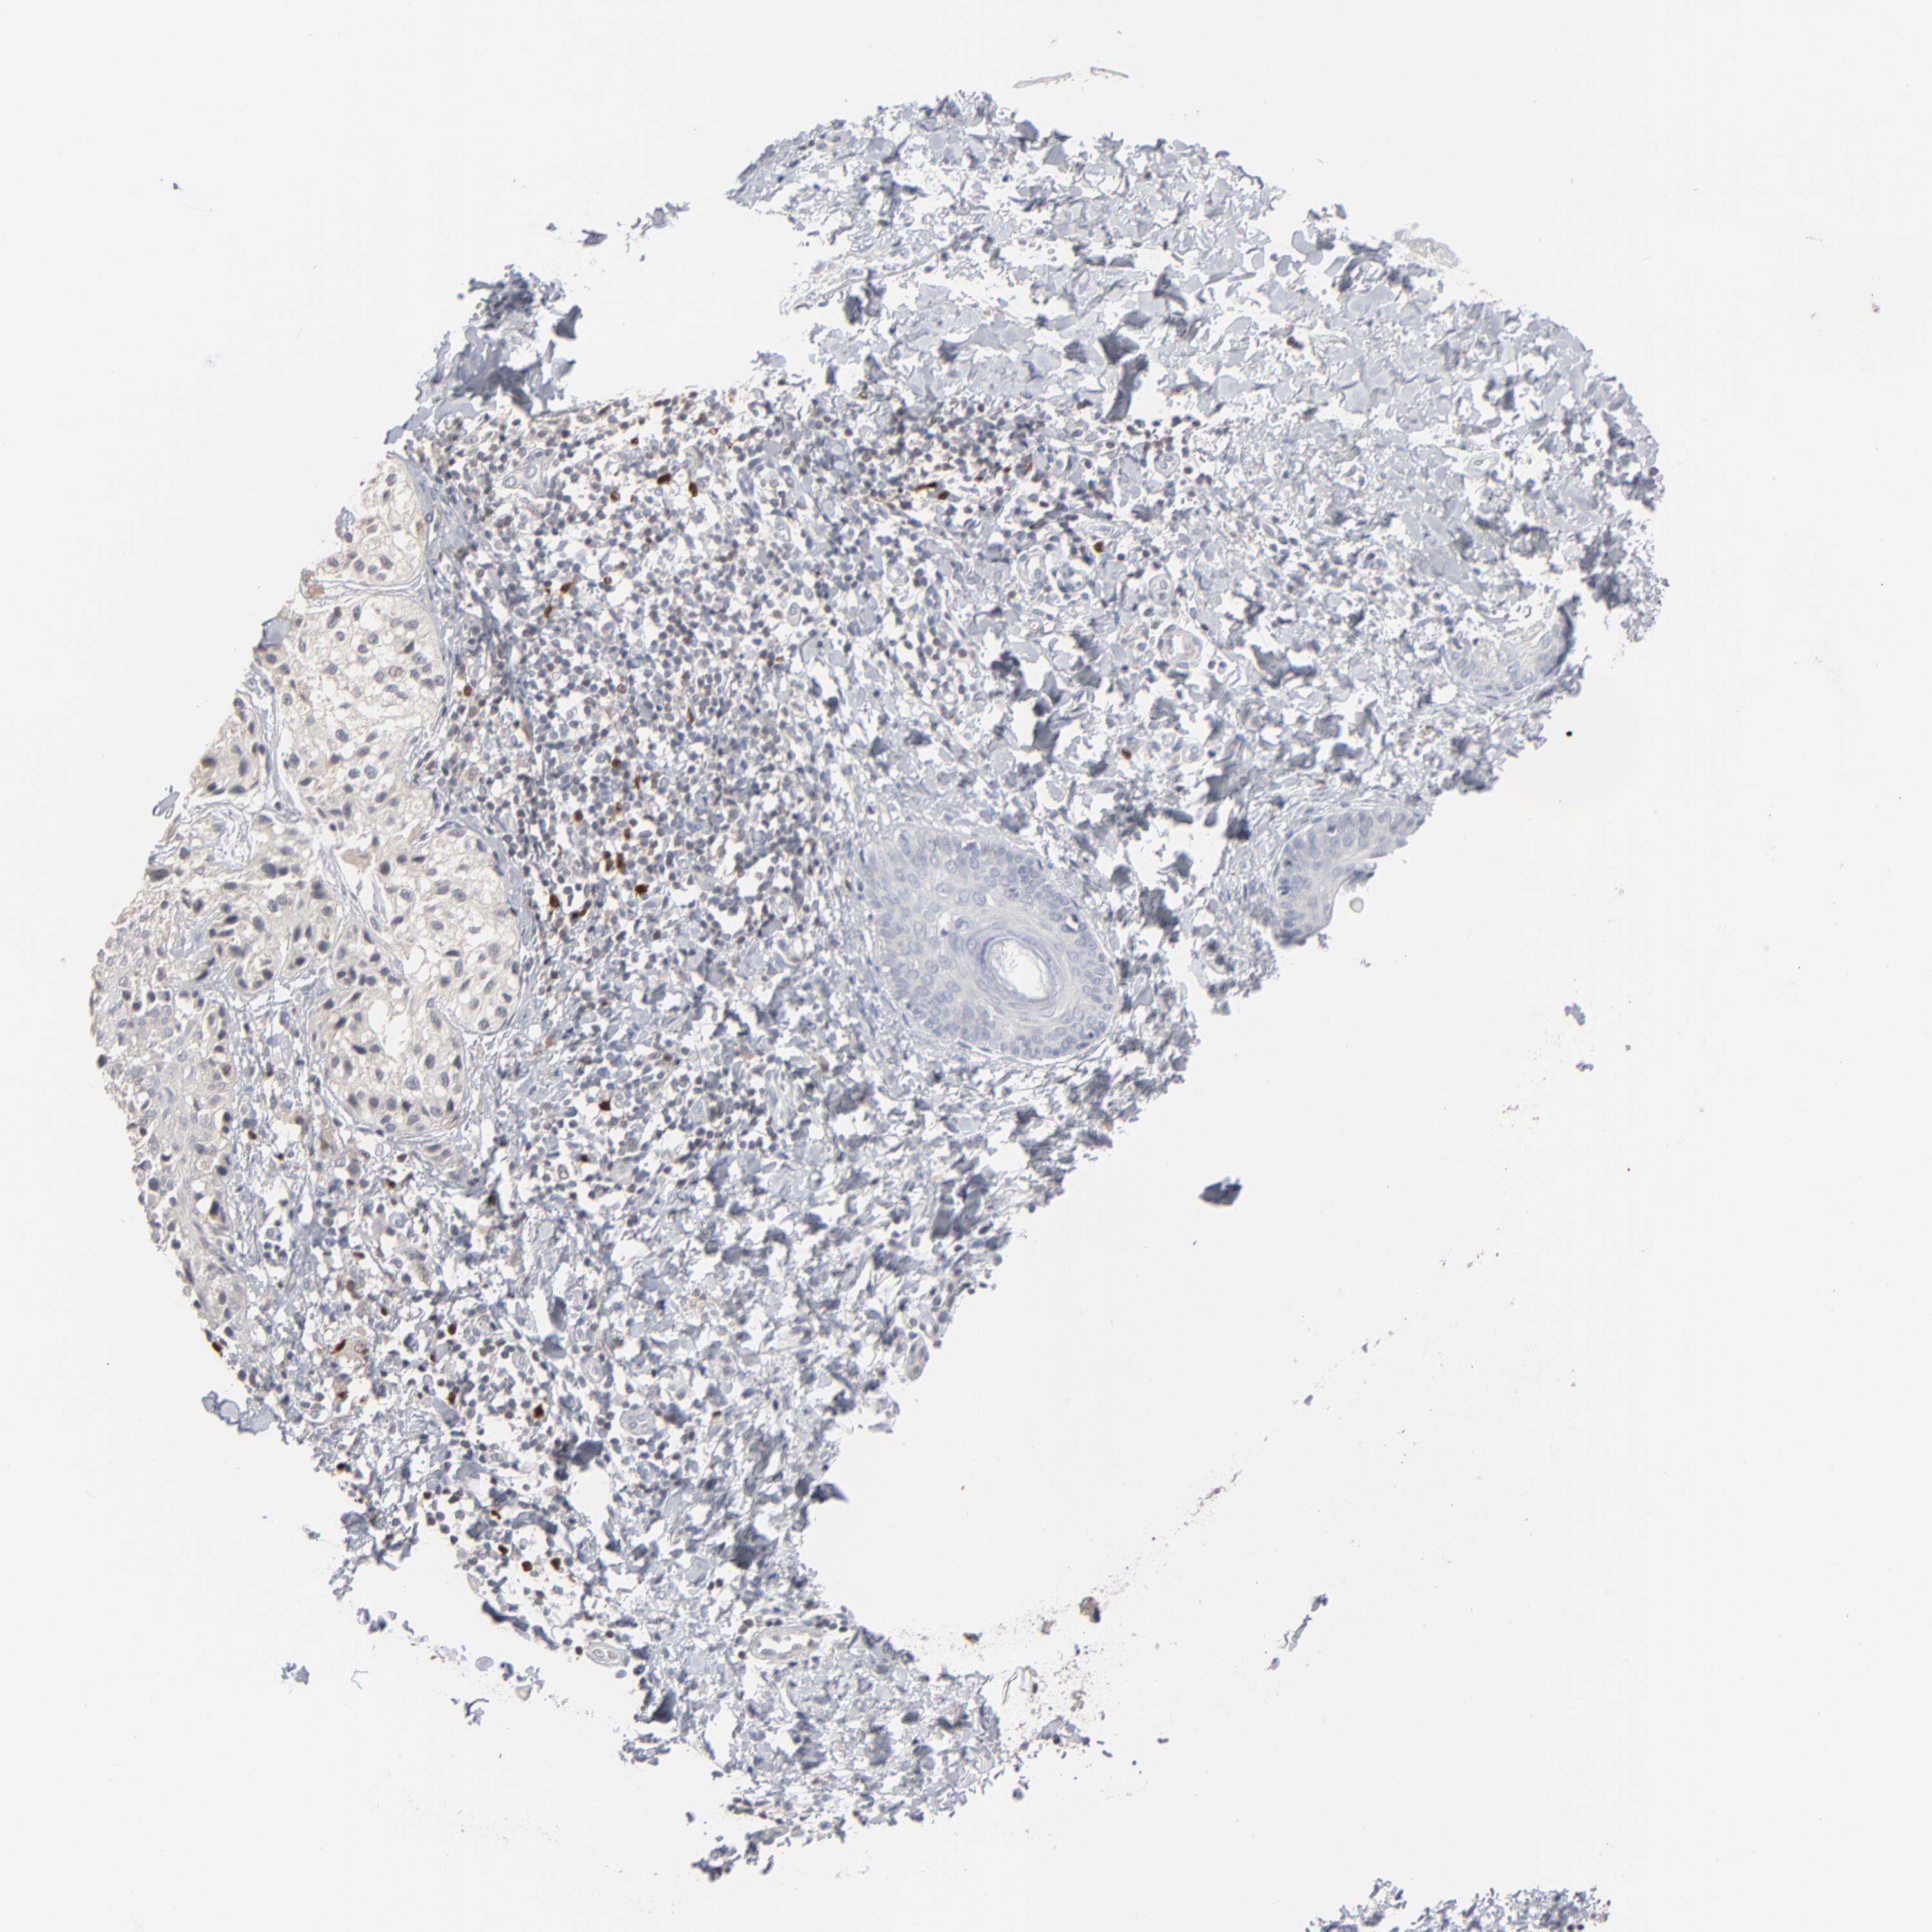

MELANOMA - Protein expressioni

A mouse-over function shows sample information and annotation data. Click on an image to view it in a full screen mode. Samples can be filtered based on level of antibody staining by selecting one or several of the following categories: high, medium, low and not detected. The assay and annotation is described here.

Note that samples used for immunohistochemistry by the Human Protein Atlas do not correspond to samples in the TCGA dataset.

Antibody stainingi

Antibody staining in the annotated cell types in the current human tissue is reported as not detected, low, medium, or high, based on conventional immunohistochemistry profiling in selected tissues. This score is based on the combination of the staining intensity and fraction of stained cells.

Each image is clickable and will lead to virtual microscopy that enables deeper exploration of all samples and also displays staining intensity scores, fraction scores and subcellular localization as well as patient and tissue information for each sample.

Antibody HPA001860

Antibody CAB013108

Staining

High

Medium

Low

Not detected

Intensity

Strong

Moderate

Weak

Negative

Quantity

>75%

75%-25%

<25%

None

Location

Nuclear

Cytoplasmic/membranous

Cytoplasmic/membranous,nuclear

Malignant melanoma, NOS

Malignant melanoma, Metastatic site